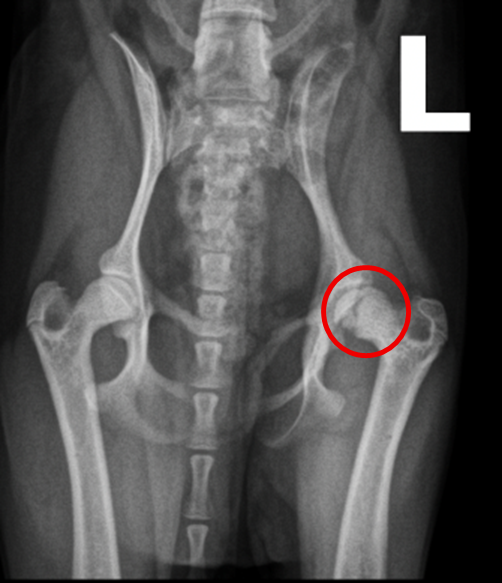

【レントゲン検査】

・同肢の骨頭にパンチアウト像および亀裂を示唆する所見がみられた (図1)

・骨折や脱臼を疑う所見は認められず